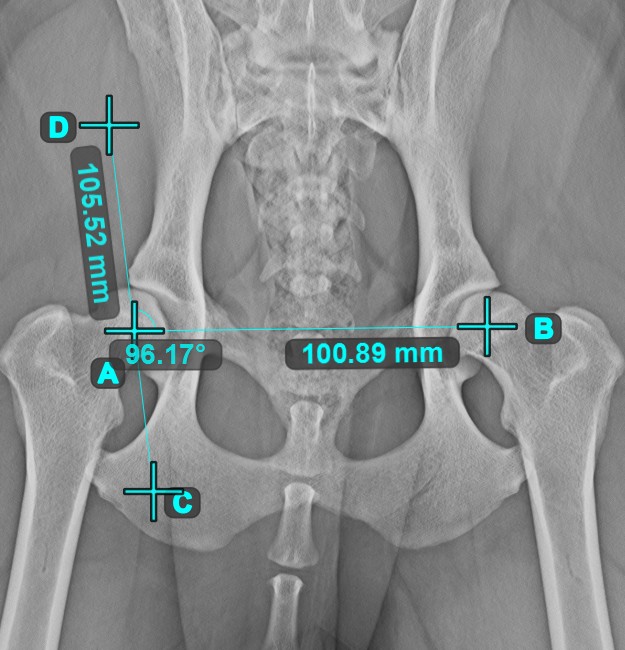

Winkel zwischen Linien¶

Berechnen Sie den Winkel zwischen zwei unabhängigen oder sich schneidenden Linien mit dem Werkzeug Winkel zwischen Linien.

Wählen Sie das Werkzeug aus der linken Symbolleiste aus und weisen Sie es einer der verfügbaren Maustasten zu. Beginnen Sie, indem Sie die erste Linie aus den bereits in der Szene gezeichneten Linien auswählen oder Start- und Endpunkt setzen, um die Linie zu erstellen. Wiederholen Sie die gleichen Schritte für die zweite Linie der Messung. Der Winkel zwischen den beiden Linien wird automatisch berechnet.

Ändern Sie die Start- und Endpunkte beider Linien mit dem Werkzeug Objekt auswählen/verschieben. Der Winkel zwischen den beiden Linien wird automatisch neu berechnet.